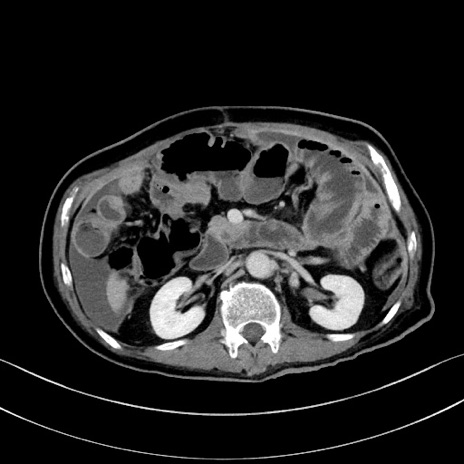

症例28(横断像)

【症例】60歳代男性

【主訴】嘔吐

【現病歴】胃癌にて胃全摘後。食思不振が悪化し、夜中に嘔吐することがある。

【既往歴】胃癌、胃全摘、脾摘、胆摘後

【データ】WBC 5900、CRP 10.56